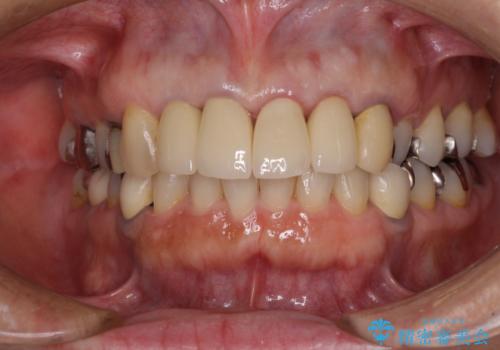

- 保険診療で装着した前歯のクラウンの変色を気にして来院された患者様です。

保険診療では樹脂を用いた素材で製作するため、水分が吸収されやすく、一緒に色素が取り込まれるために変色をしてしまいます。

また、裏打ちに主に銀を用いた金属材料を使用するため、金属自体が黒くなったり、イオンとなり溶け出したりして、歯肉ラインが黒くなってしまうことがあります。

自然で透明感のある前歯になると同時に、歯茎付近の黒ずみや隙間も改善でき、患者様には大変満足していただきました。